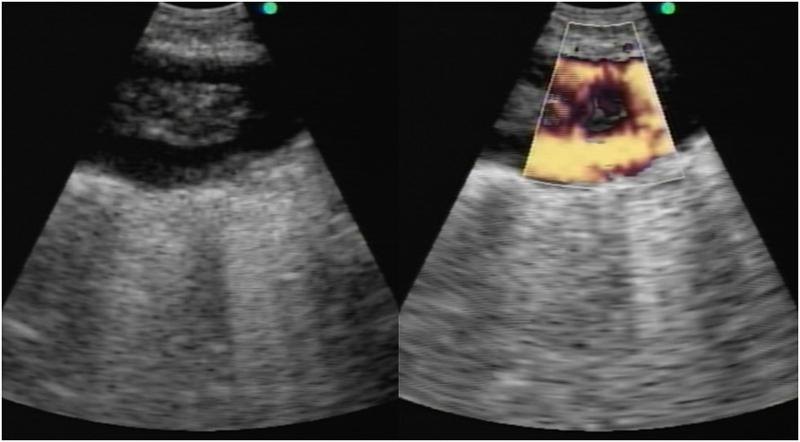

A 57-year-old female with a history of rheumatoid arthritis on chronic prednisone and methotrexate was admitted to the hospital with acute hypoxic respiratory failure. She was initially admitted to the medical intensive care unit (ICU) with a diagnosis of pneumonia but she did not improve with antibiotics. Given her risk factors for opportunistic infections, a diagnostic bronchoscopy with linear endobronchial ultrasound (EBUS) was performed. An abnormality in the pulmonary artery was noted (Figure 1).

Figure 1